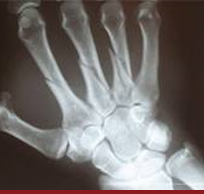

Önkol, Elbileği Ve El Yaralanmaları